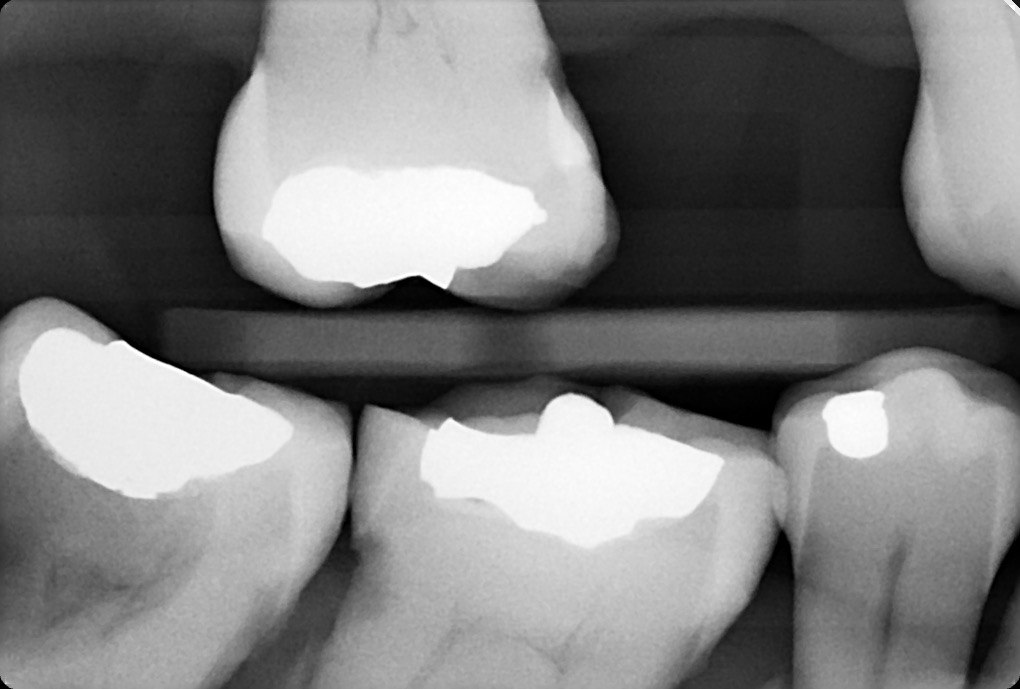

10. What condition can be seen on the teeth # 1.5 and 1.4?

11. What is the radiolucency on the teeth # 1.1, 1.2, 1.3?

12. What is the condition showed by the arrow?